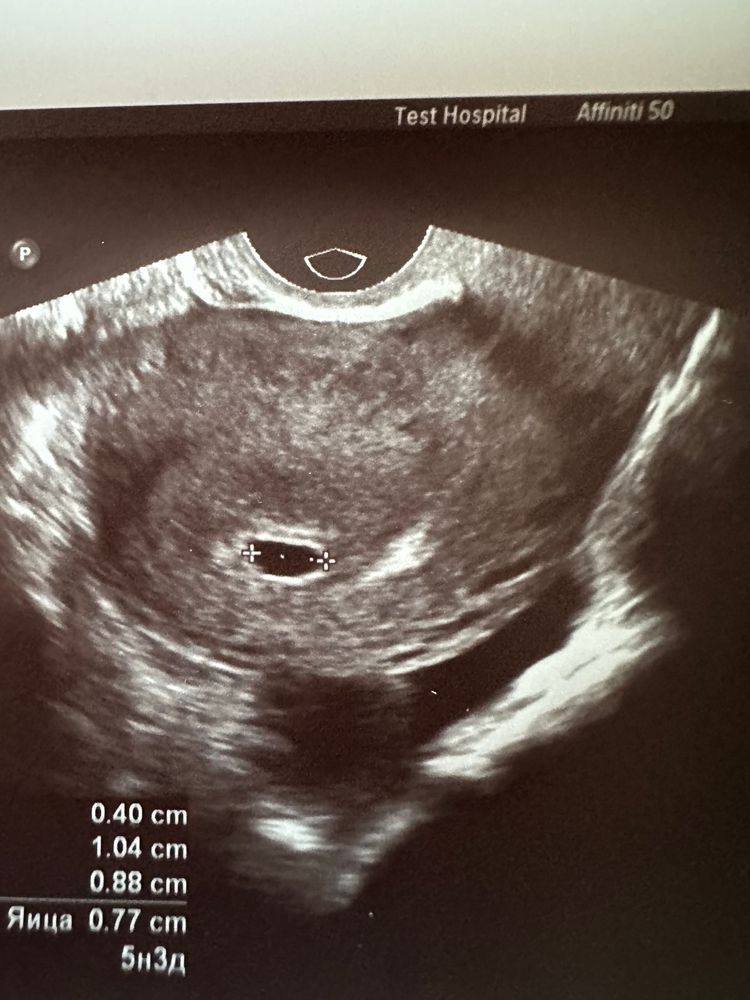

Диана, Изображение Вот пер Изображение Вот первое узи , видно точку

10.08.2023